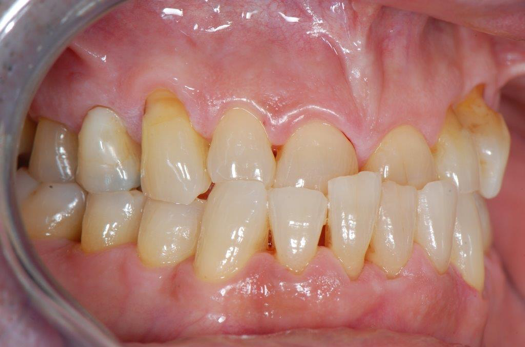

Fig 11. Preoperative healed sites.

Figure 11

Figure 10 through Figure 13 show the preoperative x-ray and the sequence of beginning with healed sites through the surgical placement of the implants. The implants were protected by an Essix-style wound-protection removable retainer for approximately 12 weeks. After the integration phase, the implants and the natural dentition were prepared using traditional crown-and-bridge high-speed diamond and zirconia cutting burs to remove decay and existing restorative materials, to complete and refine the natural-tooth structures to receive full-crown coverage, and to prepare and refine gingival margins of the zirconia implants where needed.